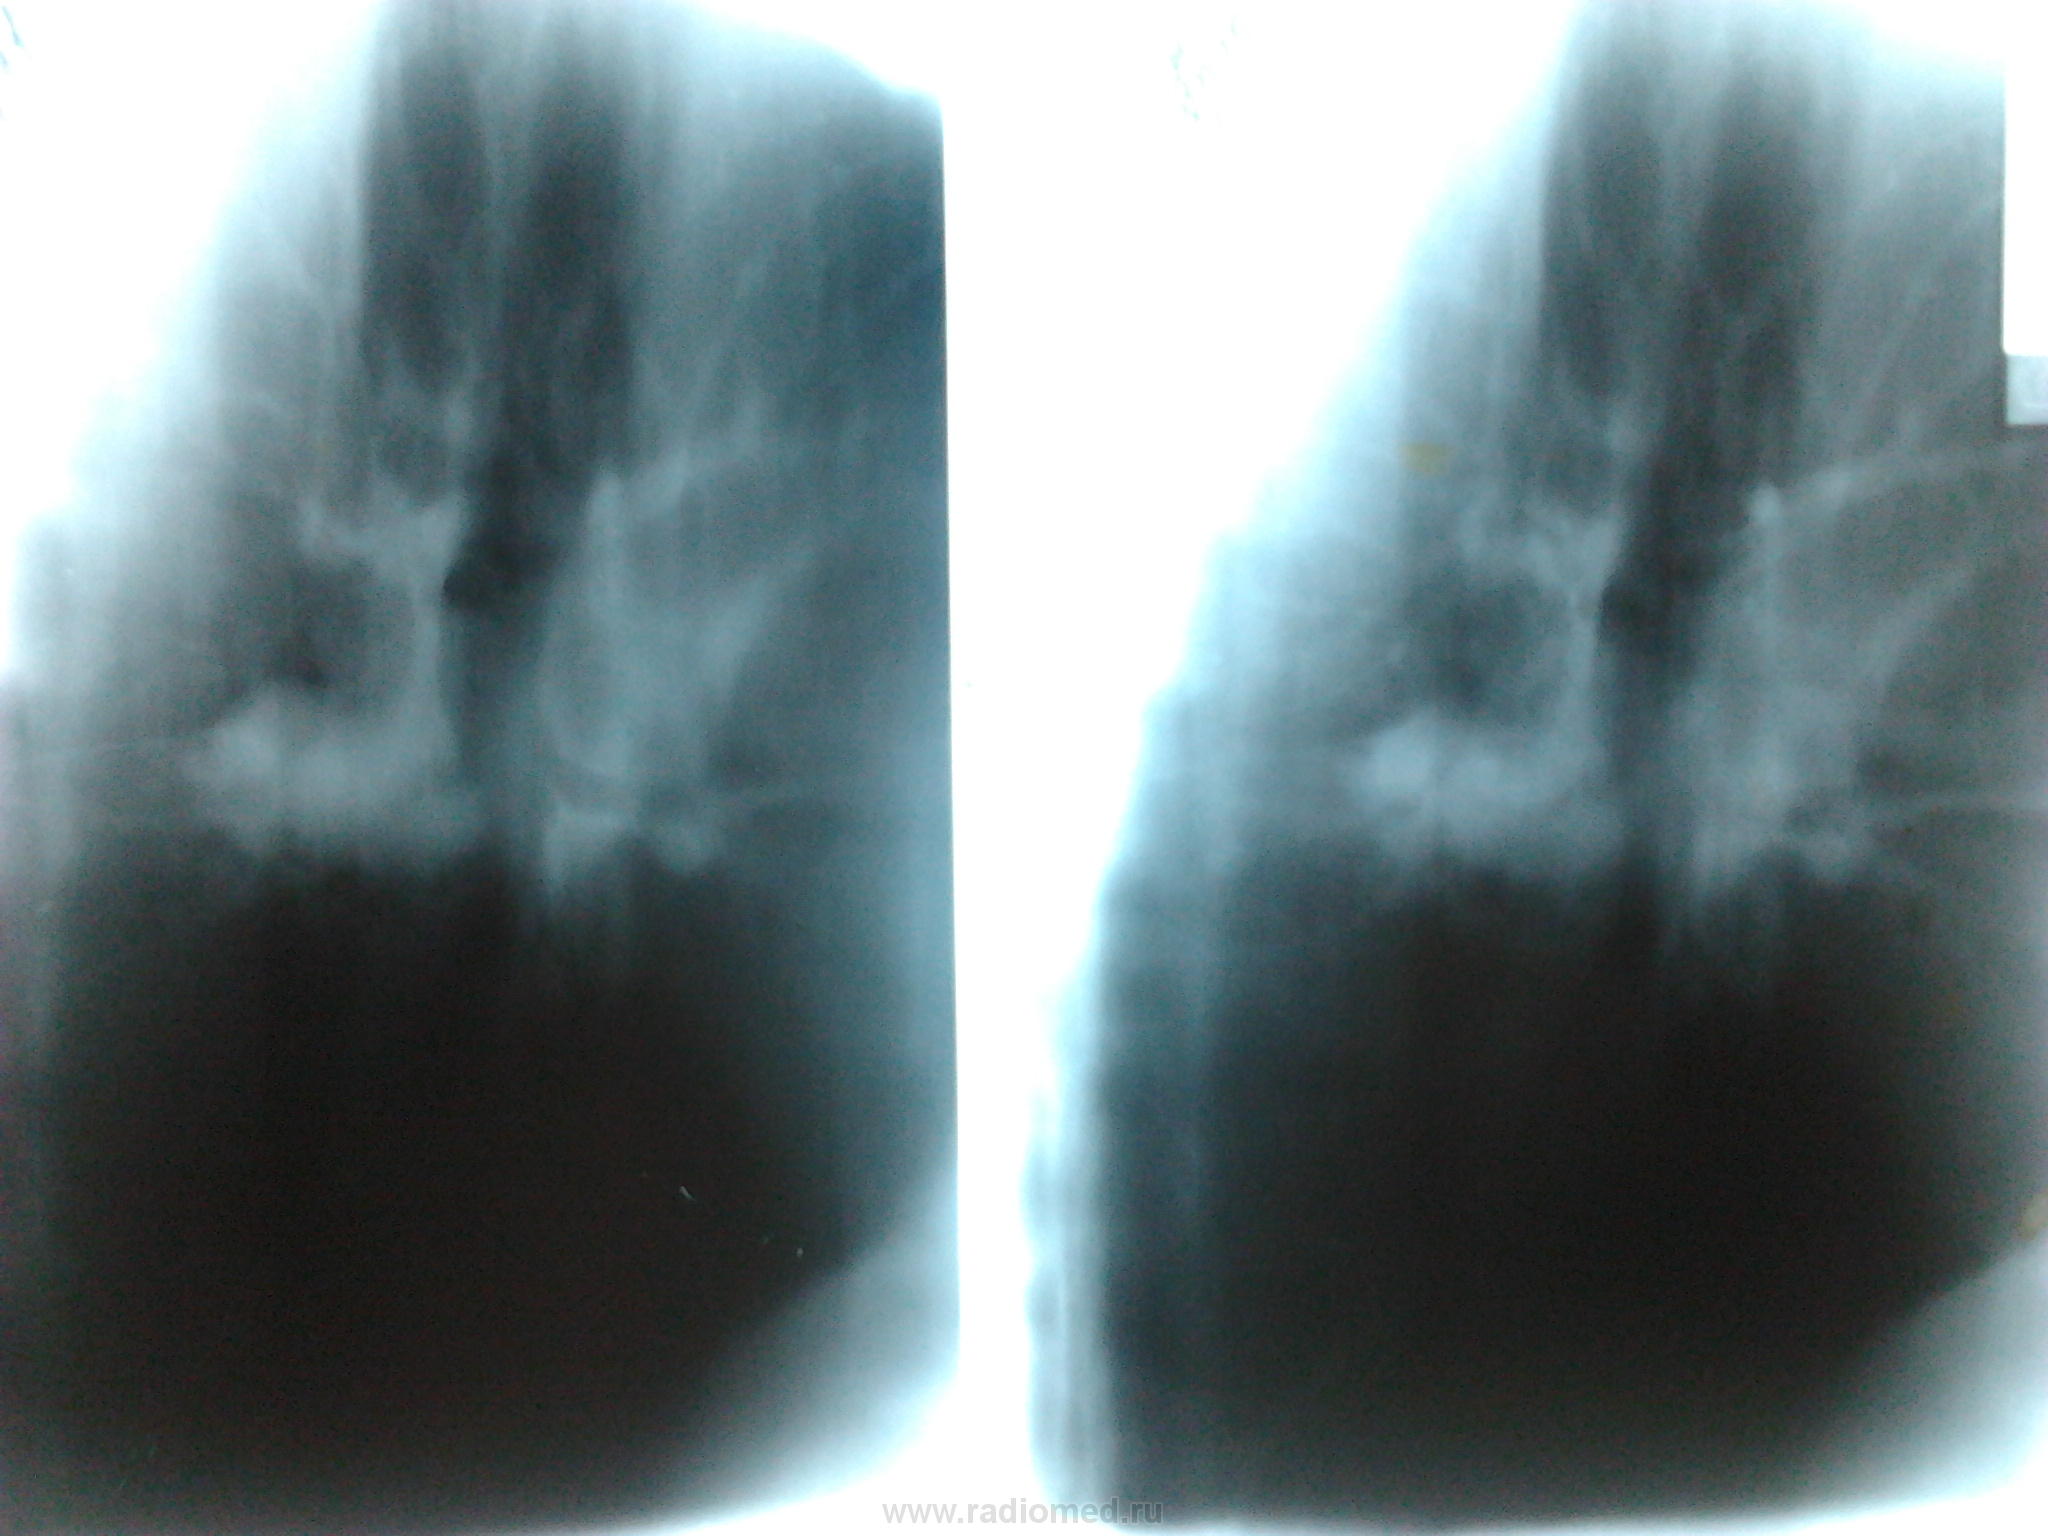

Великолепные томограммы в боковой проекции с отчётливой картиной поражения 6 сегментарного бронха.

[/ Ее я тоже исключала . Но почувствовала неладное в S6-посмотрите внимательно,-в его основании -тень некрупного отграниченного инфильтрата с распадом. На обзорном снимке-в прикорневой зоне -участок инфильтрации, вот и выясняла, что ж это такое. Написала,что процесс "наш", а дальше-дело техники. В результате (была и ФБС )-туберкулома с распадом. И туберкулез сегментарного бронха S6. И туберкулез ВГЛУ.Предвижу вопрос-не ВИЧ, в том-то и дело. Необычно,но бывает.

Алкс! Спасибо за совет,но снимки "пожестче"специально "заказала",чтобы "пробить" л/у и бронхи посмотреть. Именно так и обнаружила туберкулому с распадом (для Nkolas'а).А щипцовая ФБС была под контролем экрана, т.е. моим,-там тоже видно было,что распад.Результат гистологии тоже подтвердил то,что уже и так было видно.Про ВИЧ ведь специально написала-см.выше в посте N 14. И поэтому тоже необычно. Да,Сергей! Зря,наверное,так рано опубликовала результат. Надо было Вас всех подождать. Потомить еще. В следующий раз тогда уж. Еще случаи будут, не переживайте.